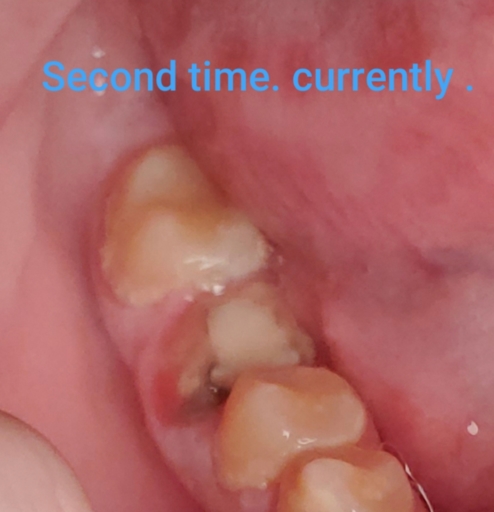

So I’ve been having gum pain in between my tooth and the tooth with the crown and the dentist told me that my crown was not properly fitted so bacteria is leaking inside and I most likely have an infection down below. I also have gingirifros I guess from pregnancy and one molars enamal is toraltngone and has some holes he suggests I get a crown there and one on top to prevent damage to the top one. I see way to many crown work going on and it’s expensive. He thinks that my crossbite caused it and suggested I also use a night guard in case of grinding. What are your suggestions and based on the photo below what do you think?